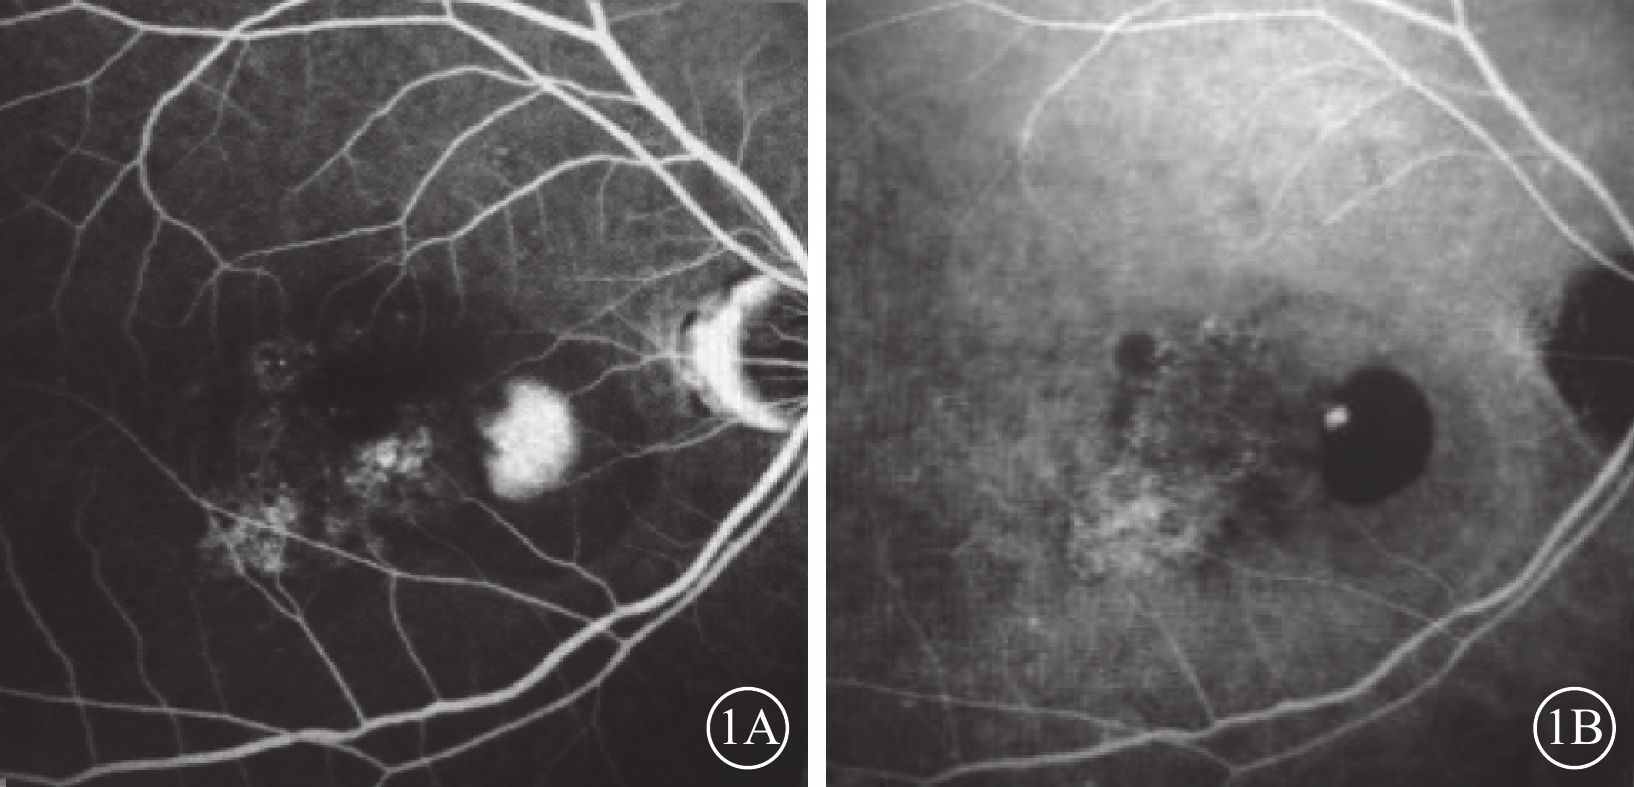

出血性PED在彩色眼底照相中表現為局部片狀或大片狀病灶,顏色從深紅到黑紅不等,周圍可伴滲出(圖3A);在cSLO成像中表現為相應區域的深綠色或暗紅色病灶(圖3B~3E),藍光反射、綠光反射、紅外反射成像均弱,與HD-OCT觀察到的PED位置一致(圖3F)。

出血性PED在彩色眼底照相中表現為局部片狀或大片狀病灶,顏色從深紅到黑紅不等,周圍可伴滲出(圖3A);在cSLO成像中表現為相應區域的深綠色或暗紅色病灶(圖3B~3E),藍光反射、綠光反射、紅外反射成像均弱,與HD-OCT觀察到的PED位置一致(圖3F)。

本研究結果顯示,PCV的漿液性PED在cSLO偽彩圖中表現為綠色或深綠色病灶,在紅外反射中呈現明顯弱反射暗區,藍光反射和綠光反射較弱。該觀察結果與Tan等[10]描述一致。而出血性PED則表現為深紅色病灶,綠光反射、藍光反射和紅外反射均呈現明顯弱反射。因為激光成像的原理是依靠不同波長激光而獲得不同層次的視網膜成像,藍光反射、綠光反射和紅外反射分別呈現視網膜淺層、中層和深層的結構。炫彩成像的過程中,依據眼底不同病變對不同波長的激光吸收、反射和透射的程度不同,顯示為相應波長激光反射的綜合圖像:藍光反射強度對應藍色成分,綠光反射強度對應綠色成分,而紅外反射強度對應紅色成分,3種反射的相對強弱決定病灶的顏色。水對光譜中的紅外部分表現出強烈的吸收,因而積液、水腫在紅外反射圖像中顯示為明顯的弱反射。因此,漿液性PED在紅外反射中呈現明顯暗區。紅外光被吸收多,反射弱;藍光和綠光吸收少,反射相對較強。并且,PED向視網膜內層隆起,病灶位于綠光反射區間,因此漿液性PED呈現綠色。血液對420~575 nm的光譜吸收率最高,反射弱;而紅外光吸收率最低,反射強[11]。因此,出血性PED在藍光反射和綠光反射出現明顯弱反射;炫彩成像中,藍光、綠光吸收多,反射弱;紅外光吸收少,相對反射較強,因此呈現紅色病灶。

本研究結果顯示,PCV的漿液性PED在cSLO偽彩圖中表現為綠色或深綠色病灶,在紅外反射中呈現明顯弱反射暗區,藍光反射和綠光反射較弱。該觀察結果與Tan等[10]描述一致。而出血性PED則表現為深紅色病灶,綠光反射、藍光反射和紅外反射均呈現明顯弱反射。因為激光成像的原理是依靠不同波長激光而獲得不同層次的視網膜成像,藍光反射、綠光反射和紅外反射分別呈現視網膜淺層、中層和深層的結構。炫彩成像的過程中,依據眼底不同病變對不同波長的激光吸收、反射和透射的程度不同,顯示為相應波長激光反射的綜合圖像:藍光反射強度對應藍色成分,綠光反射強度對應綠色成分,而紅外反射強度對應紅色成分,3種反射的相對強弱決定病灶的顏色。水對光譜中的紅外部分表現出強烈的吸收,因而積液、水腫在紅外反射圖像中顯示為明顯的弱反射。因此,漿液性PED在紅外反射中呈現明顯暗區。紅外光被吸收多,反射弱;藍光和綠光吸收少,反射相對較強。并且,PED向視網膜內層隆起,病灶位于綠光反射區間,因此漿液性PED呈現綠色。血液對420~575 nm的光譜吸收率最高,反射弱;而紅外光吸收率最低,反射強[11]。因此,出血性PED在藍光反射和綠光反射出現明顯弱反射;炫彩成像中,藍光、綠光吸收多,反射弱;紅外光吸收少,相對反射較強,因此呈現紅色病灶。